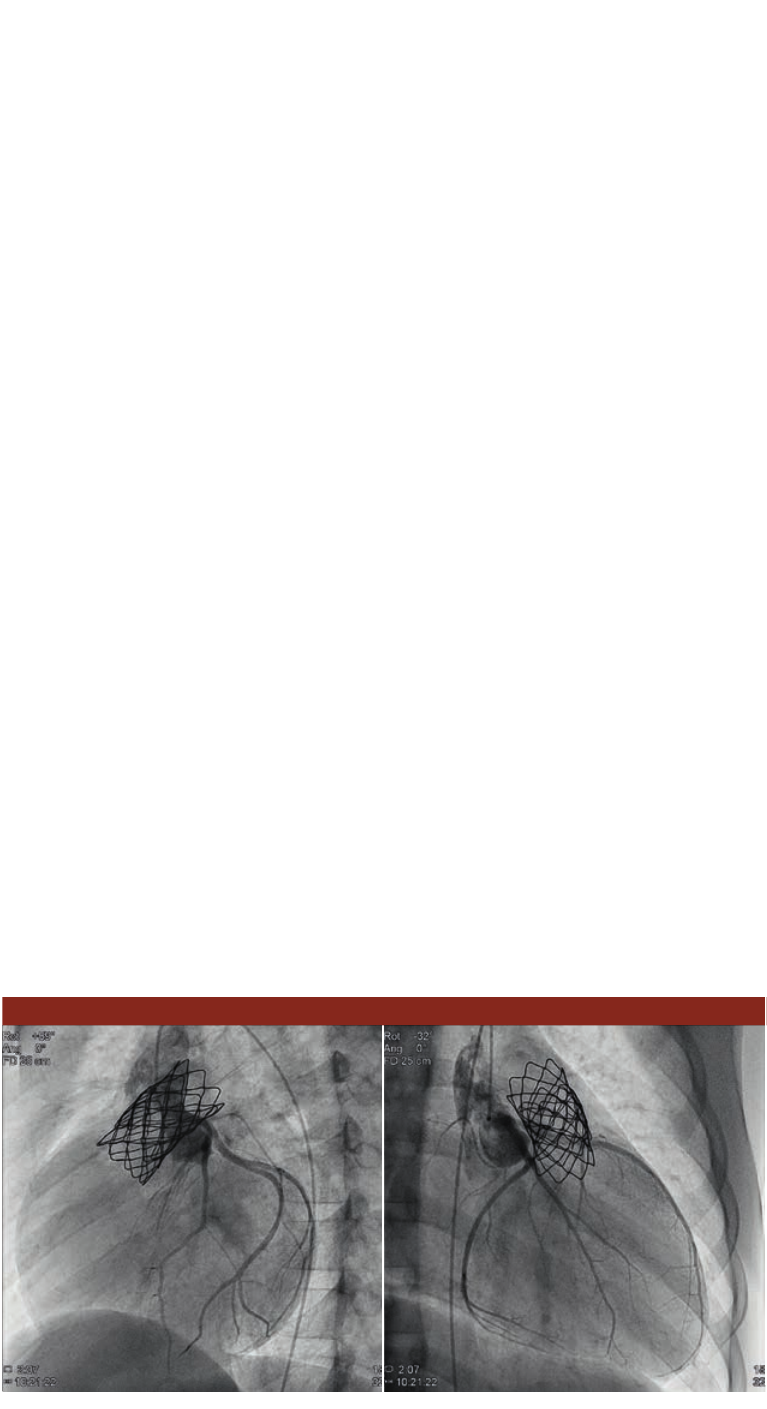

Low dose valve replacement – case 2

Inasecondcase,a10-year-oldboywassufferingfrom

severepulmonarygraftstenosisandmoderateinsufciency.

Duringtheproceduretimeof85minutesaMelody™

valvewasplacedintothisfailinggraftwhileexposingthe

patienttoonly8311mGycm2with15fps.Thisintervention

replacedasurgicalvalvereplacementtohopefullyprovide

thepatientwithenoughcapacitytostayoutoftheORfor

therestofhischildhood.

Conclusion and nal results

ThenewAlluraClaritywithClarityIQtechnologyprovides

equivalentimagequalityat50%lessdose.Thisprovidesthe

exibilitytousethesysteminapersonalizedwayforeach

procedureandpatient.

LAO 91 Cranial 0, 15 fps

Field of view: 25 cm

Angiogramdemonstratingthe

stenosiswithinthepulmonary

valve.Measurementsrevealed

aminimaldiameterof12-13mm

measuredinthemid1/3ofthe

graft,andadistaldiameterof

18-20mmjustbeforethe

pulmonarybifurcation.

Case 2: Melody™ valve implantation

3D Roadmap in AP

3D Roadmap: balloon ination of sidebranch 3D RA of stent after ballooning side branch.

3D roadmap in LAO40/Caud27

3D Roadmap in AP: overlap at bifurcation, inadequate

for intervention

TheostiumofthesidebranchisnotclearlyvisibleintheAllura

3D-RAinAPpositionbecauseofoverlappingvessels.

3D Roadmap in LAO40/Caud27: clear view on bifurcation

ThebifurcationisclearlyvisibleintheAllura3D-RAin

40LAO/27Caudalposition.

3D Roadmap: balloon ination of sidebranch

The3DRoadmapimageshowstheballooninatedinthe

sidebranch.

3D RA of stent after ballooning side branch

Apost-proceduralAllura3D-RAshowsthestentstrutsopenin

thesidebranchtoenableadequatebloodow.